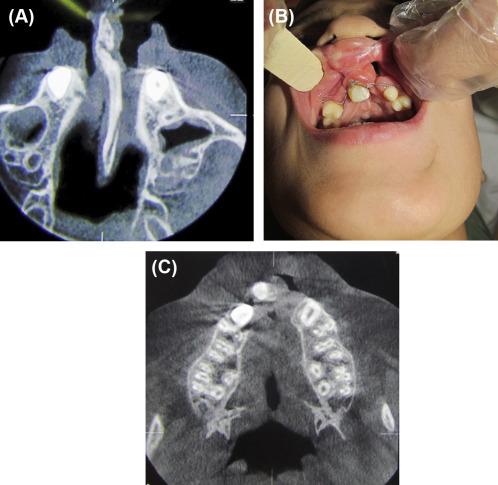

(A) Protruded premaxilla and thick bony septum. (B) Clinical result 1 month ...

Figure 3.

(A) Protruded premaxilla and thick bony septum. (B) Clinical result 1 month after the operation. Interdental wiring is used for further stabilization. The right side was bone grafted simultaneously with premaxillary osteotomy. (C) Cone beam computer tomography (CBCT), 3 months after the operation shows premaxilla, correctly aligned with lateral segments (one side bone grafting).

The patient was an 11-year-old boy with an unsuccessful previous operation for the closure of a bilateral alveolar cleft. The premaxilla was protruded and extruded. It was managed with this new technique (Figure 3). This patient was followed up for 2 years.